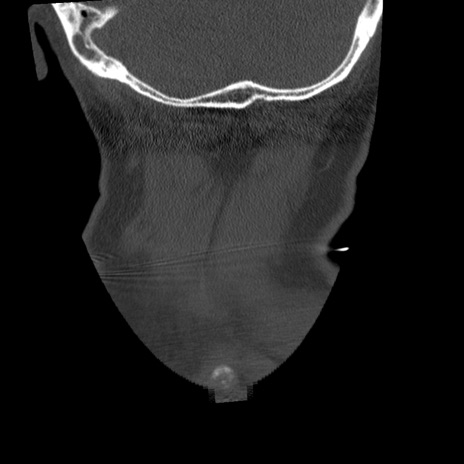

症例50 頚椎CT(冠状断像)

【症例】60歳代女性

【主訴】後頭部〜右後頸部にかけての痛み

【現病歴】本日飲食店でコーヒーを飲んでいたところ、突然後頭部〜右後頸部にかけて痛みが出現し、右上肢の感覚障害を伴ったため救急要請。

【身体所見】脳神経学的に明らかな異常所見を認めず。右上肢に軽度の感覚障害あり。

異常所見と診断は?

横断像